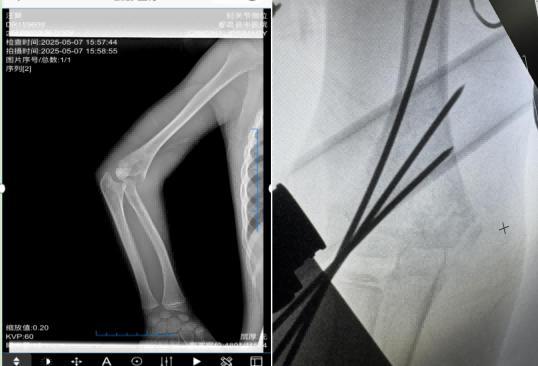

7岁的患儿乐乐(化名)则因摔倒后肘部受伤,确诊为儿童肱骨髁上骨折。该部位骨折若处理不当,可能影响肘关节功能及血管神经。团队采用闭合复位经皮内固定术,在手法复位骨折后,通过皮肤穿刺植入克氏针固定,全程无大切口。术后复查,乐乐肘关节活动恢复正常,未留下功能障碍。

78岁的李爷爷则因不慎摔倒导致股骨颈骨折,考虑到老年患者身体耐受度低,团队实施闭合经皮空心钉内固定术:在C型臂引导下精准定位,通过3个微小切口植入空心钉,手术耗时仅40分钟。术后配合康复指导,有效降低了老年患者长期卧床引发的并发症风险。